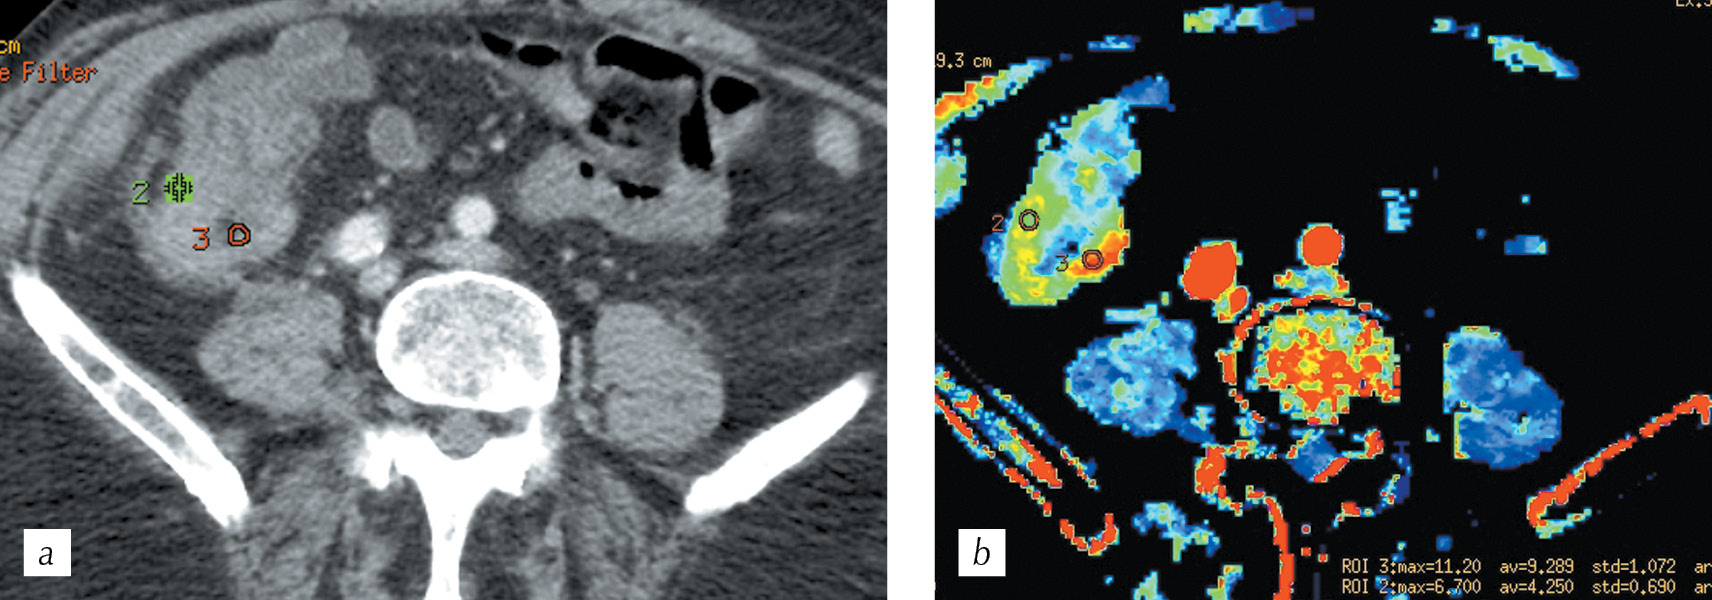

It was revealed that for a moderately differentiated adenocarcinoma, the visual assessment of the parametric cards is characterized by a clear difference between the tumor vascularization and the adjacent intact intestinal walls. Further, the boundaries of infiltrative changes in the intestinal wall during PCT were wider when compared to that obtained during standard spiral CT (Fig. 7, a, b). Following the placement of the ROI 2 labels in the tumor, and ROI 3 labels in the wall of the intact intestine, we obtained tables of digital values that demonstrate clear differences in the blood flow velocity indicator as BF in the tumor wall minand intact intestine was 112 ml/100g per min and 16 ml/100 g per min, respectively (Fig. 8, a). The density–time plot indicates functional changes in the tumor tissue in the form of the rise in curve 2 after 15 s of scanning, with a peak at 28 s and 3 s after the appearance of a peak in the afferent vessel. The green curve indicate that changes in the intact intestinal wall had a relatively straight course without significant peaks (Fig. 8, b).

Fig. 7. HCT, multiplanar reconstruction in the axial plane in the portal phase (a) and СT perfusion, parametric map of the blood flow (b) with ROI 2 in the invasive part of the tumor and ROI 3 in the intact intestinal walls

Рис. 7. Спиральная компьютерная томография, мультипланарная реконструкция в аксиальной плоскости в портальную фазу сканирования (a) и перфузионная компьютерная томография, цветная параметрическая карта скорости кровотока (b) с метками ROI 2 в инвазивной части опухоли и ROI 3 в смежных интактных стенках кишки

Fig. 8. Summary tables of perfusion parameters (а), the density-time graph (b) for the ROI 2 area in the tumor and ROI 3 in the intact intestinal wall

Рис. 8. Сводные таблицы числовых значений (a), график «плотность – время» (b) для меток ROI 2 в опухоли и ROI 3 в интактной стенке кишки

Fig. 10. HCT. Multiplanar reconstruction in the axial plane to the arterial phase (a) and CT perfusion, parametric map of blood volume (b) with ROI 2 marks in the most vascularized area and ROI 3 in the contralateral intestinal wall

Рис. 10. Спиральная компьютерная томография. Мультипланарная реконструкция в аксиальной плоскости в артериальную фазу сканирования (a) и перфузионная компьютерная томография, цветная параметрическая карта объема кровотока (b) с метками ROI 2 в наиболее васкуляризированном участке и ROI 3 в контралатеральной стенке кишки